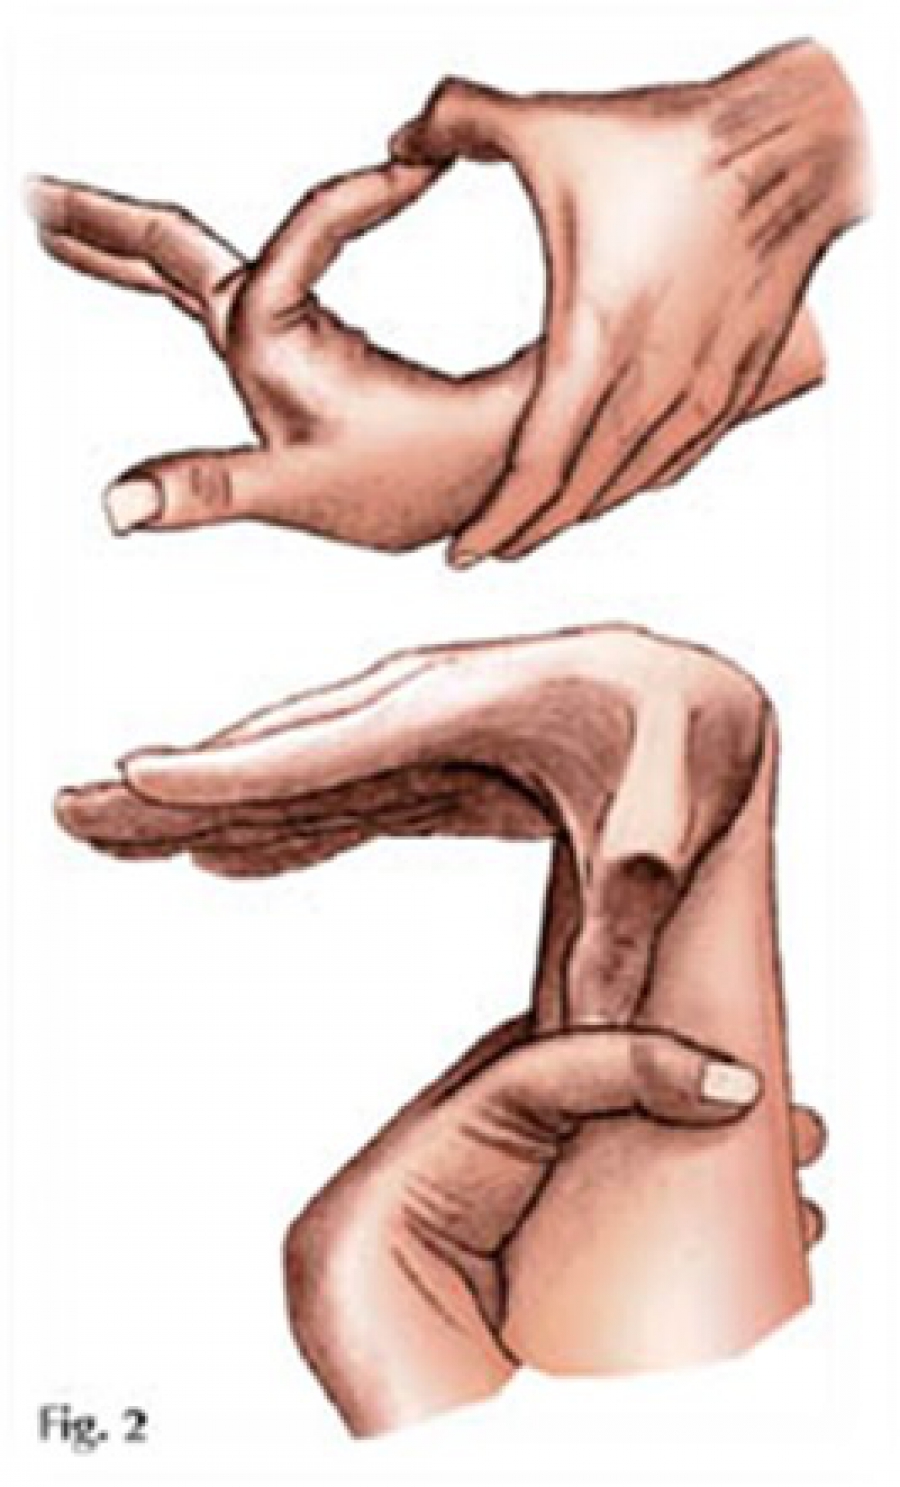

Sindrom marfana tema nauchnoj stati po klinicheskoj medicine chitajte besplatno tekst nauchno issledovatelskoj raboty v elektronnoj biblioteke kiberleninka (Тип файлу jpg)

Sindrom Marfana Tema Nauchnoj Stati Po Klinicheskoj Medicine Chitajte Besplatno Tekst Nauchno Issledovatelskoj Raboty V Elektronnoj Biblioteke Kiberleninka

Sindrom marfana tema nauchnoj stati po klinicheskoj medicine chitajte besplatno tekst nauchno issledovatelskoj raboty v elektronnoj biblioteke kiberleninka (Тип файлу jpg)

Sindrom Marfana Tema Nauchnoj Stati Po Klinicheskoj Medicine Chitajte Besplatno Tekst Nauchno Issledovatelskoj Raboty V Elektronnoj Biblioteke Kiberleninka